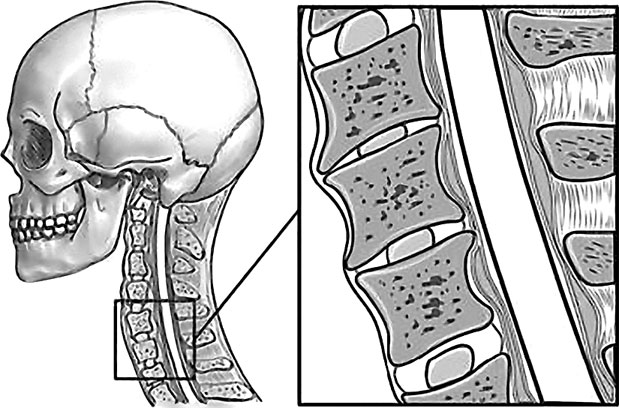

Подобные симптомы могут вызываться спазмами как позвонков, так и мышц шеи. К примеру, перенапряжение затылочных мышц зачастую ведет к головным болям и к проблемам со зрением. Так что шейный отдел позвоночника, состоящий из 7 позвонков, должен иметь и достаточную длину, и определенную статику (рис. 67).

Рис. 67. Нормальная статика шеи. Правильный физиологический изгиб: А=А1

А что в действительности имеем мы? Обычно, даже при здоровом позвоночнике (только где его найдешь?), он начинает с возрастом деформироваться, «проседать», менять статику. Появляется симптом смещенной вперед и запрокинутой назад головы (рис. 68).

Рис. 68. Гиперлордоз шейного отдела позвоночника: B > B1

В результате небольшой физиологический изгиб гипертрофируется, что ведет к проваливанию шейных позвонков вглубь шеи, особенно интенсивно при «сидячей» работе. Формируется гиперлордоз шейного отдела позвоночника.